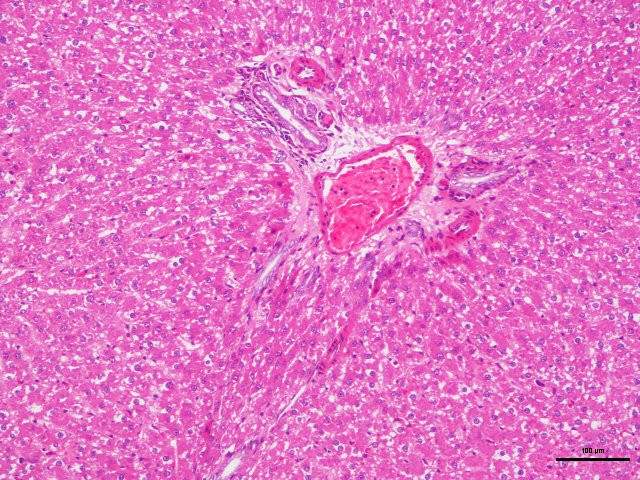

样片参考:

肝